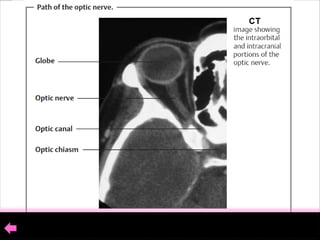

The optic nerve extends from the posterior pole of the eye to the optic

chiasm with total length of (35–55mm) . The nerve consists of :

1- An intraocular portion (Optic Disk) .

2- An intraorbital portion.

3- An intracranial portion.